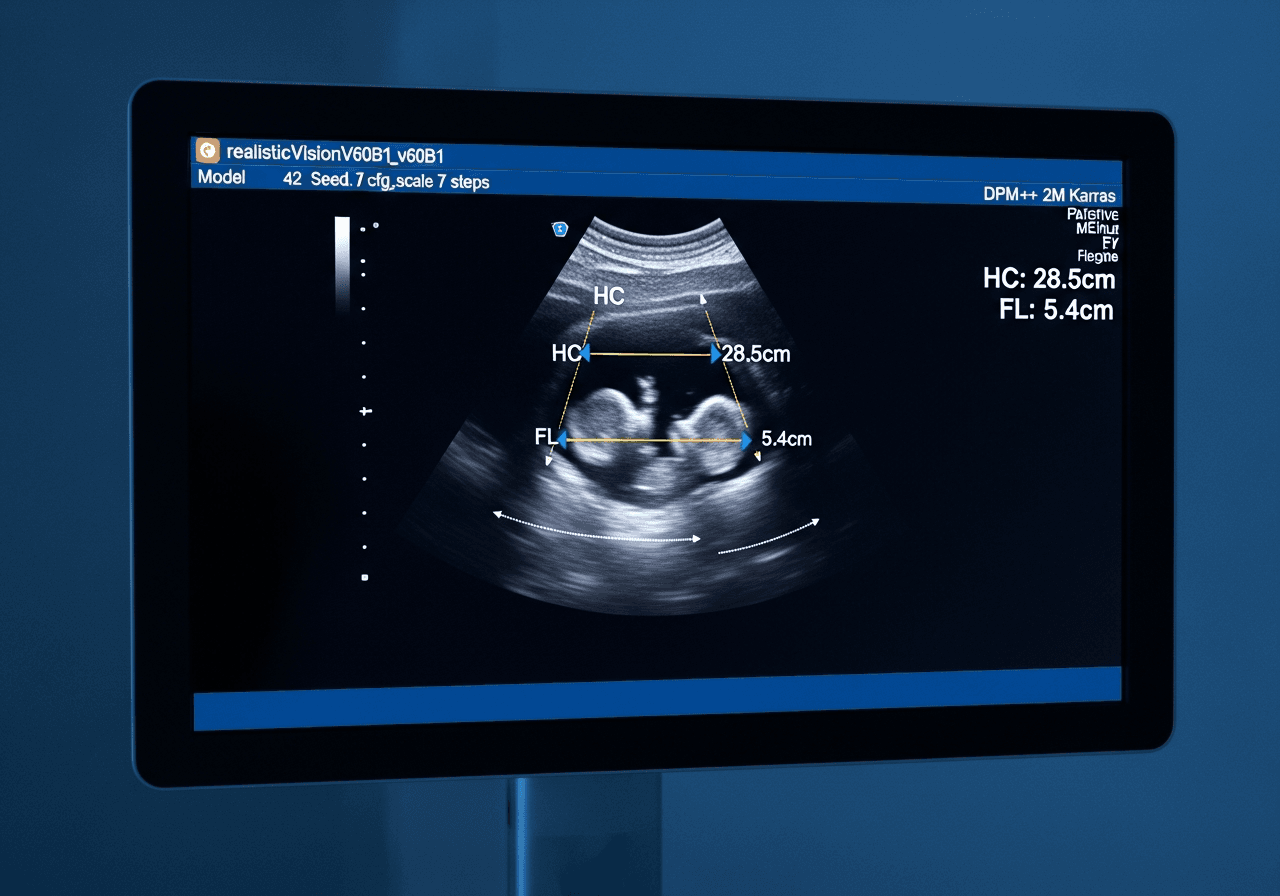

Biométrie fœtale

Les mesures de votre bébé expliquées